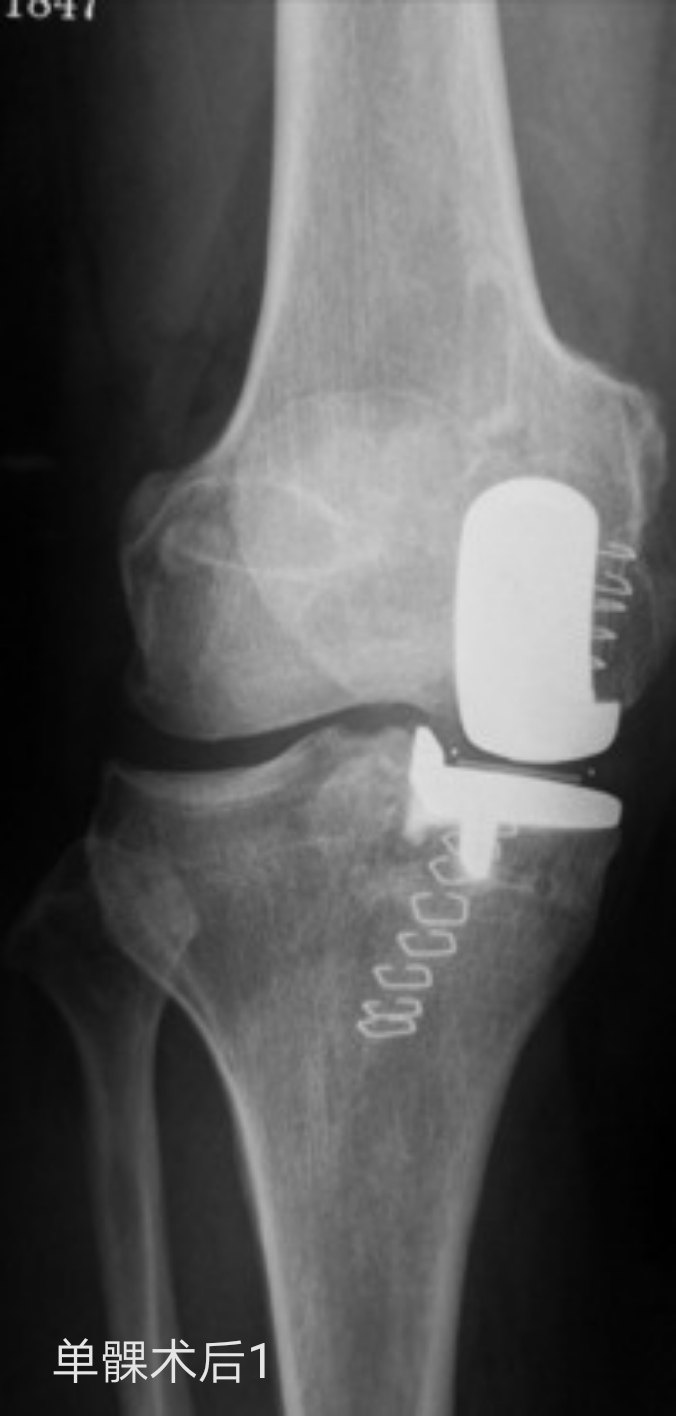

目前关节外科大夫所说的“保膝”手术,主要是指高位胫骨截骨术(HTO)和人工单髁表面置换术(UKA)两种,二者的共通点是在缓解疼痛症状的同时可以最大程度的保有您自身“原装”的膝关节骨质,不同的是前者HTO往往适用于年纪轻些的患者,而后者UKA往往适用于年纪稍大些的患者。当然,这只是非常笼统的说法,具体适合哪一种手术还是需要经过关节外科大夫的详细检查评估才能确定的。

下面就有两种手术的照片,请大家感受了解一下。如果您还有什么疑问,请您毫不犹豫的咨询熊奡大夫吧!